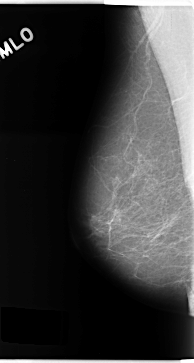

C_0157_1.LEFT_MLO

LEFT_MLO LINES 4728 PIXELS_PER_LINE 2464 BITS_PER_PIXEL 12 RESOLUTION 50 OVERLAY

FILE: C_0157_1.LEFT_CC.OVERLAY

TOTAL_ABNORMALITIES 3

ABNORMALITY 1

LESION_TYPE MASS SHAPE OVAL MARGINS MICROLOBULATED

ASSESSMENT 4

SUBTLETY 5

PATHOLOGY MALIGNANT

TOTAL_OUTLINES 1

ABNORMALITY 2

ABNORMALITY 3